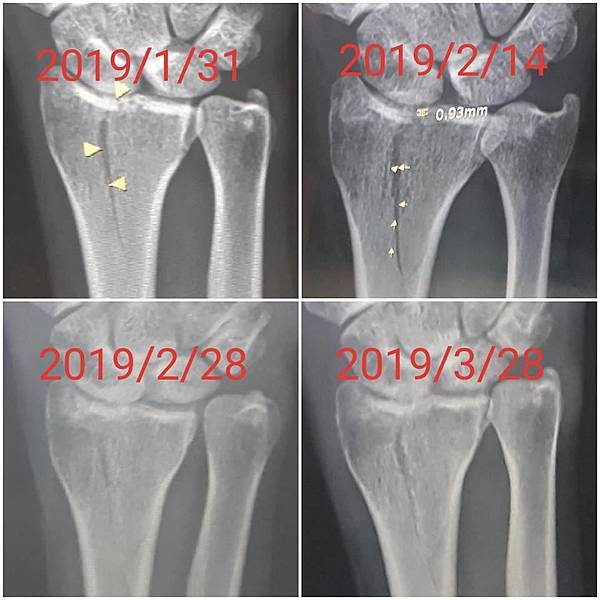

今日所拍的X光照↓

這三次回診的X光片,相較前兩次,今天已經癒合許多了↓

或許今天是228放假日,來醫院看病的人蠻多的,我們等了一段時間才被叫到。進到診間後,黃醫師調出X光資料,發現橈骨已癒合很多了,讓我感到很吃驚,兩個星期前還是很明顯的骨裂,現在已經看不太到了(小純說,一定是峰王膠原飲發揮了功效,這兩週內,膠原蛋白喝了八罐了)。黃醫師說,我的手腕護具可以拿掉了,我拿起護具後,黃醫師拉了我的手腕做一些轉動的動作,還是有些痛,黃醫師叫我要多做熱敷,手可以開始做復健了,也可以讓手開始做一些事情,但避免提重物,兩個星期後再回診看角度。

之後,我去照了X光,因為一個月前照X光,感覺已經快好了,我以為今天去照,骨頭應已癒合的差不多了。結果照出來之後,竟然還能看的到裂痕,讓我大吃一驚。唉....可能要等一陣子才會好。

今日所拍攝的X光照↓

最近四次所拍的X光↓